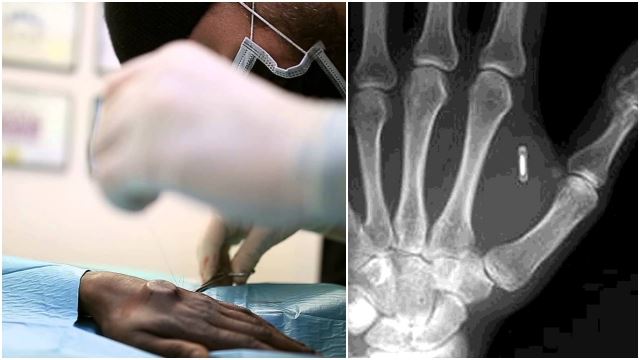

Salah Satu Syarikat Di UK Tanam Cip Dalam Tangan Pekerja